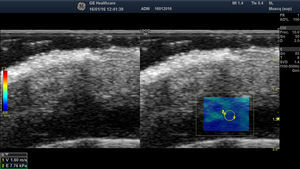

Elastography of Normal Skin and AdnexaThe stiffness of healthy skin varies according to the cutaneous layer being studied. The dermis is more rigid than the subcutaneous cellular tissue16 (Fig. 2, A, B). In the subcutaneous cellular tissue, the septa are more rigid than the fat lobules. Blood vessels, like the peripheral nerves, are not very rigid in comparison to the surrounding subcutaneous cellular tissue.16

A, Strain elastography of normal skin. Note the strain ratio of the dermis and the fat (SR=1.86), which indicates that the dermis is stiffer than the subcutaneous tissue.

E indicates epidermis; D, dermis; TCS, subcutaneous cellular tissue.

B, Shear wave elastography of the dermis of the scalp. In the lower right corner, note the parameters of velocity and pressure in the region of interest (yellowish-green rectangle).